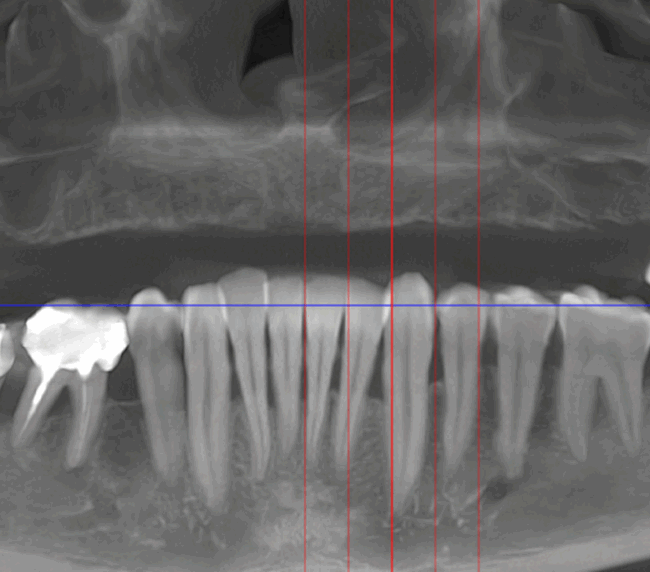

Caz 2